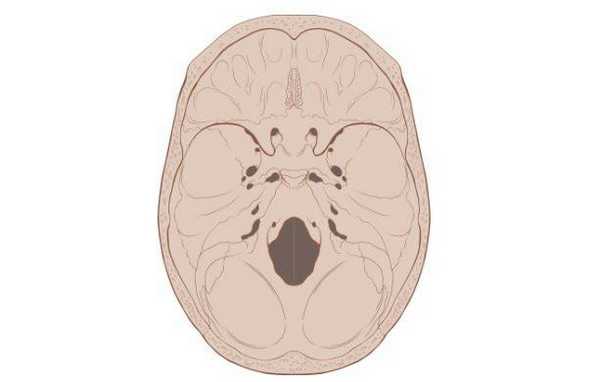

![Схематическое изображение основания черепа]()

Схематическое изображение основания черепа

Основание черепа - область, образуемая затылочной, височными, решетчатой, лобной и клиновидной костями. Внутренняя поверхность данной анатомической структуры играет роль площадки, на которой покоится головной мозг. Через большое отверстие затылочной кости проходит ствол мозга. Наружная поверхность основания черепа богата нервными волокнами, кровеносными сосудами, связками и сухожилиями.